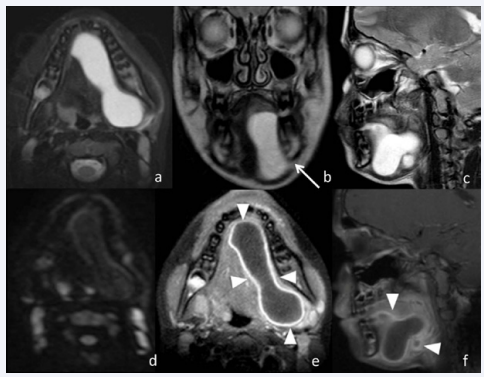

After 3 days an MRscan of the neck was performed. T2- weighted (w) andT1-w fast spin echo sequences before and after intravenous contrast administration were obtained in the axial, coronal and sagittal planes, with the addition of fatsaturation in axial plane; diffusion weighted images (DWI) were also performed in axial plane. The examinationdemonstrateda conspicuous left side lesion (measuring 7.5x2.8x4.5 cm), unilocular, hourglass shape, with sharp margins, emanating from the sublingual space, extending into the adjacent submandibular space. The masswashomogeneous, hypointenseon T1-w, markedly hyper intenseon T2-w and did not demonstrate restricted diffusion. After contrast administration the mass showed linear and thick enhancing wall(Figure 2).

Figure 2 MR imaging of plunging ranula

(a-c) Axial T2-w fat sat image (a), coronal (b) and sagittal (c) T2w images; d) axial diffusion weighted image (DWI);e-f) axial (e) and sagittal T1-w fat sat images. MRI showsan extensive left side lesion with sharp margins in sublingual and submandibular spaces. The lesion has homogeneous high signal intensity on T2-w sequences (a-c), without high signal on DWI (d) and with linear and thick enhancing wall (arrowhead). In this case there is the dehiscence of the mylohyoid muscle (arrow).

Anteriorly it extended to the submentalregion of both sides.Posteriorly and inferiorly itplunged through mylohyoid muscle.Posteriorly and medially extended to parapharingeal space. Adjacent soft tissue planes and structures appeared compressedand displaced; the mandible appeared normal with no evidence of destruction. The diagnosis of plunging ranula was postulated, after differential diagnosis from other swellings of the anterior-lateral neck region. Excision of the mass was carried out under general anesthesia via an intraoral technique, approaching the floor of the mouth. The left sublingual gland was excised with ranula marsupialization. Histopathological examination of the excised mass confirmed the diagnosis of mucous extravasation cyst, revealing a connective tissue with inflammatory cell response, lining the lumen. No recurrence has been observed atone-year follow up

Our case is a rare extensive plunging ranula with multicompartmental involvement; the clinical diagnosis was difficult because the initial clinical presentation was submandibular swelling and only later involved the floor of the mouth. Furthermore lesion heterogeneous echogenicity and multicompartmental extensiondid not allow the correct diagnosis by ultrasound.Thick enhancing wall on MRIis an atypical finding for plunging ranula, nevertheless this technique allowed a correct diagnosis due to signal intensity characteristics, the ability to assess ramifications in deeper neck spaces, to evaluate the anatomic relationship with adjacent soft tissue, and especially to identify a connection to the sublingual space.